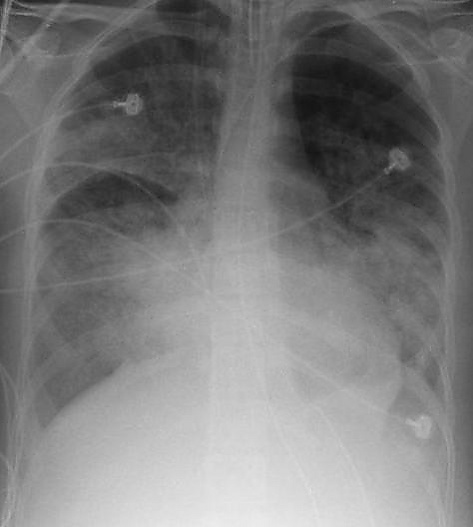

При рентгенографии лёгких видны двусторонние диффузные инфильтраты, иногда — плевральный выпот. Такие признаки неспецифичны и также характерны для кардиогенного отёка лёгких, что затрудняет дифференциальную диагностику[15][16]. Компьютерная томография показывает негомогенную инфильтрацию лёгких в определённых отделах (в задненижних отделах у лежачих больных)[17]. Это объясняется зависимым от силы тяжести распределением отёка лёгких и сдавлением вышележащими отёчными отделами лёгких[18].